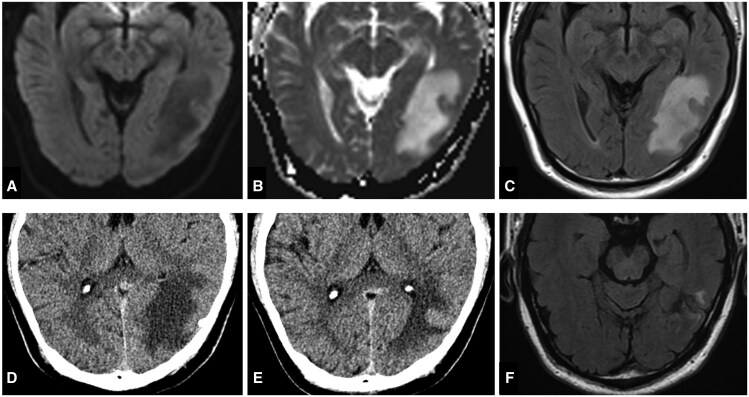

一名63岁男性表现为急性发作的间歇性头晕、视觉障碍和左颞头痛。检查发现左侧乙状窦有硬脑膜动静脉瘘(dAVF),分类为Cognard IIb型。使用线圈和Onyx进行成功的经静脉栓塞治疗,导致dAVF完全解决,没有立即并发症。然而,栓塞后3天,患者出现头痛、头晕、视觉不适和失读。MRI显示左侧颞枕区血管源性水肿,原因是静脉流出梗阻。尽管给予依诺肝素和地塞米松治疗,患者仍出现进行性症状,包括物体命名困难、记忆力下降和非惊厥性癫痫发作。随访影像显示水肿改善和稳定的最小局灶性胶质瘤。这例罕见的患者在硬脑膜AVF血管内栓塞后出现失读症,强调了术后监测的重要性,并提示预防性抗凝治疗可以降低可能的并发症风险。

A 63-year-old male presented with acute onset of intermittent dizziness, visual disturbances, and left temporal headache. Investigations revealed a dural arteriovenous fistula (dAVF) at the left sigmoid sinus, classified as Cognard type IIb. Successful therapeutic transvenous embolization was performed using coils and Onyx, resulting in complete resolution of the dAVF without immediate complications. However, 3 days post-embolization, the patient developed headache, dizziness, visual discomfort, and alexia. MRI findings suggested vasogenic oedema in the left temporo-occipital area due to venous outflow obstruction. Despite treatment with enoxaparin and dexamethasone, the patient experienced progressive symptoms including difficulty in object naming, memory decline, and nonconvulsive seizures. Follow-up imaging indicated improvement of oedema and stable minimal focal gliosis. This rare case of a patient developing alexia following endovascular embolization of a dural AVF highlights the importance of post-procedural monitoring and suggests potential benefits of prophylactic anticoagulation to reduce the risk of probable complications.